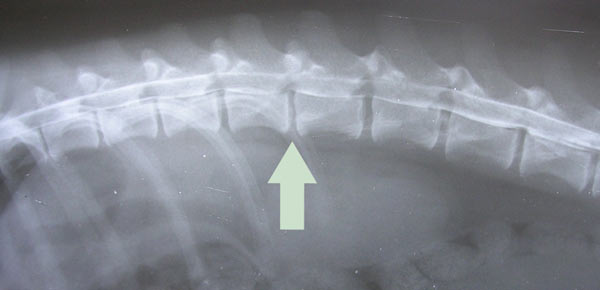

- Рентгенография. С её помощью можно определить состояние позвонков и травматические повреждения.

- компьютерная томография (КТ) – тоже хороший метод, но грыжу в данном случае можно диагностировать по косвенным признакам – изменениям в косной структуре; мягкие ткани на КТ видны не будут;

- рентгенография – оценка состояния позвоночника может быть проведена только по косвенным признакам – состоянию костных тканей и высоте пространства между позвонками, что говорит о истончении диска и возможном наличии грыжи.

- Рентгеновская компьютерная томография (менее детальная картина позвоночника и взаимоотношения его структур, несет дозовую лучевую нагрузку);